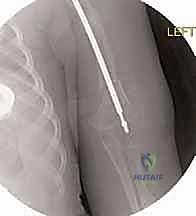

قبل العملية، يقوم الدكتور هطيف بإجراء دراسة شاملة لصور الأشعة السينية (X-rays) المأخوذة بدقة، لحساب زوايا التقوس بدقة متناهية، وتحديد نقاط بضع العظم (أماكن القص)، واختيار الحجم والطول المناسبين للمسمار التلسكوبي.

الخطوة الرابعة: إدخال المسمار التلسكوبي

بعد تقويم العظم وجعله مستقيماً كحبات المسبحة على خيط، يتم إدخال السلك الدليلي (Guide Wire). ثم يتم إدخال الجزء الخارجي (الأنثوي) من المسمار التلسكوبي وتثبيته في الجزء العلوي من العظم (Epiphysis).

بعد ذلك، يتم إدخال الجزء الداخلي (الذكري) من المسمار عبر الجزء السفلي من العظم وتثبيته في المشاشة السفلية. هذا التصميم العبقري يضمن حماية العظم بالكامل من الداخل.

عانت رؤى من كسور متكررة في عظم القصبة (الساق) بمجرد محاولتها الجري. أظهرت الأشعة هشاشة شديدة وتقوساً أمامياً. بعد استشارة الأستاذ الدكتور محمد هطيف، تقرر إجراء التدخل الجراحي المحدود. تم تصحيح التقوس بنجاح باهر، وبفضل المسمار التلسكوبي الذي ينمو معها، عادت رؤى للعب مع أقرانها بثقة وأمان.